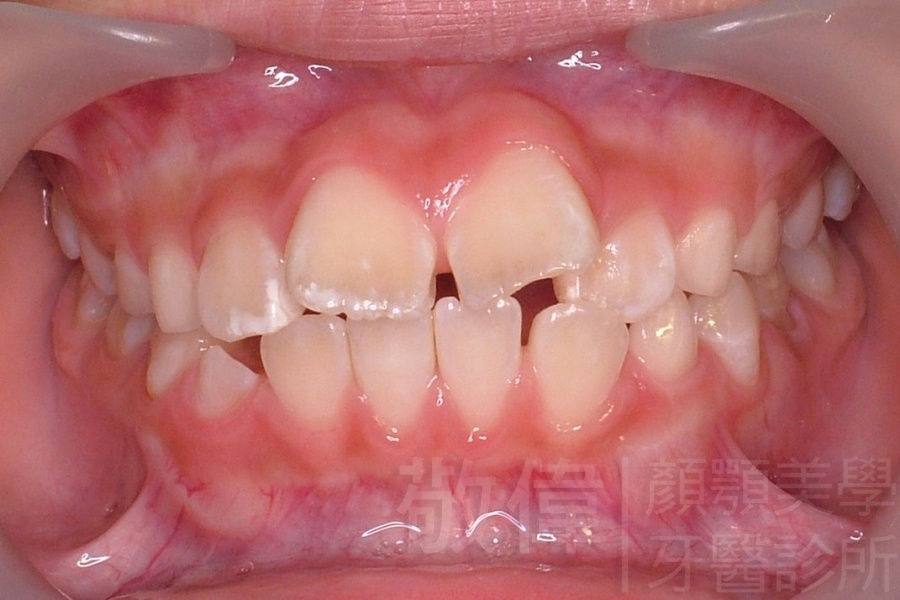

齒顏矯正/上顎暴牙且牙齒極度混亂

矯正前-右   矯正前-正   矯正前-左

<個案說明>

上顎暴牙且牙齒極度混亂,經由矯正之後,臉型大幅度改善,牙齒的排列更加的整齊健康。相較於之前眼神充滿精神,自信心展現無遺。